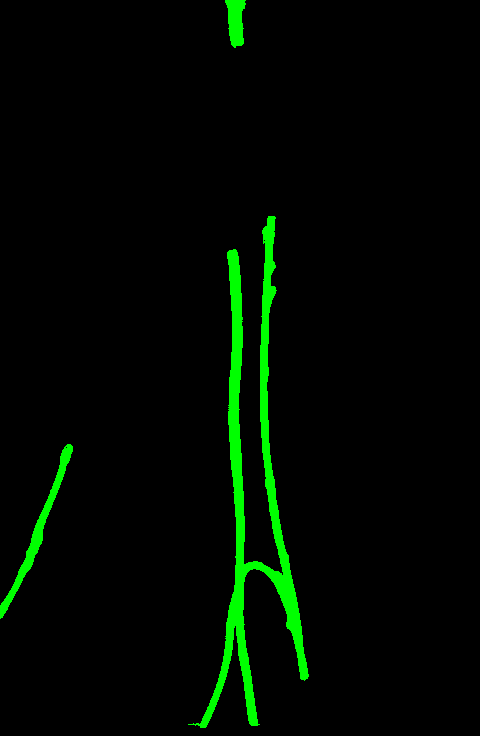

Qualitative visual examples of the raw catheter likelihood maps obtained directly from the network without any postprocessing are shown in Figure 5. It can be seen that the proposed network at the highest scale (scale 3) achieves the best visual appearance as compared to the other methods. The maps from the proposed network at scale 2 and scale 3 look much cleaner than w/oR and fcn8s. We would attribute this to the iterative refinement of the detection results by using the recurrent module. When comparing results from the proposed network at different scales, we can see that the likelihood map from the smallest scale contains almost all line-like structures, including not only catheters but also ribs and ECG leads. This is because catheters, ribs, ECG leads look similar at a smaller scale. These irrelevant line-like structures are gradually filtered out in higher scales because catheters, especially UVCs and UACs, begin to appear as two parallel edges whereas ribs and ECG leads continue to appear as a single solid line.